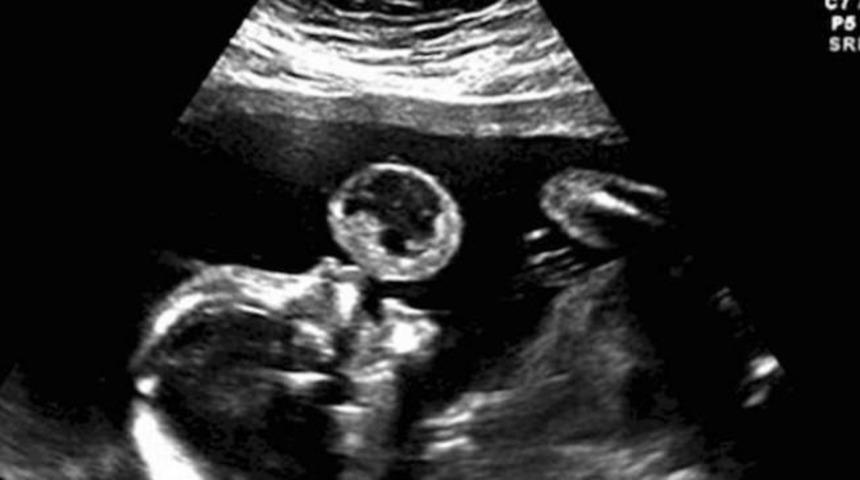

ABD’li anne Tammy Gonzales, bebeğinin ağzındaki baloncuk gibi görünen tümörü fark etti. Doktoruna yönelttiği ilk soru bunun tehlikeli olup olmadığıydı.

Yapılan araştırmalar sonucunda bu baloncuğun 100 binde 1 görülen ölümcül bir tümör olduğu anlaşıldı. "Teratoma" olarak adlandırılan bu tümör, anne karnındaki bebeğin ağzında günden güne büyüyordu.

Operasyonu gerçekleştiren Dr. Ruben Quintero santimetrelerle ifade edilebilecek ufak bir kesikten annenin karnına girdi. Karnın içine giren ufak bir kamera ve cerrahi araçlarla saatler süren operasyondan sonra doktor tümörü keserek hem küçük bebeği, hem de anneyi kurtardı. Bütün bu işlemler sırasında lokal anestezi uygulandığı için genç anne hiçbir şey hissetmese de olan bitenin farkındaydı. Aylar sonra doğum gerçekleştiğinde tümörden geriye sadece ufak bir ameliyat izi kaldı.